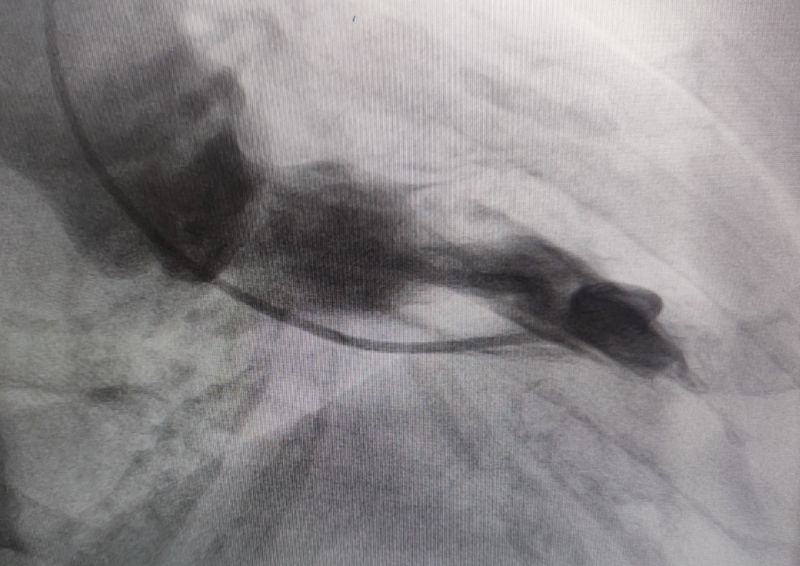

經過多輪嚴謹的術前討論,在吳棟梁院長的專業指導下,崔旭輝主任醫師團隊決定在臨時起搏器的安全保護下,為患者實施冠狀動脈造影術及室間隔化學消融術。術中,團隊通過造影精準鎖定第一穿隔支為消融靶血管。測壓數據顯示:左室壓260/15mmHg,流出道173/6mmHg,主動脈壓106/70 mmHg,壓力階差達87mmHg。隨后,團隊使用2.0X15mm預擴球囊以8atm壓力阻斷第一穿隔支遠端血流1分鐘,再次測壓時,壓力從269/7mmHg驟降至174/4mmHg,這一結果充分證實該血管正是室間隔的有效供血血管。緊接著,團隊通過SPRINTER OTW2.0×8mm球囊緩慢注入1.4ml無水酒精。10分鐘后復測,左心室壓降至136/5 mmHg,主動脈壓為112/93 mmHg。術后第2天,王女士胸悶、氣短、心悸等不適癥狀完全消失。復查心臟彩超顯示:EF值與FS值保持穩定,收縮期左室流出道血流速度降至252cm/s,PG值為25mmHg。

測壓

消融時測壓